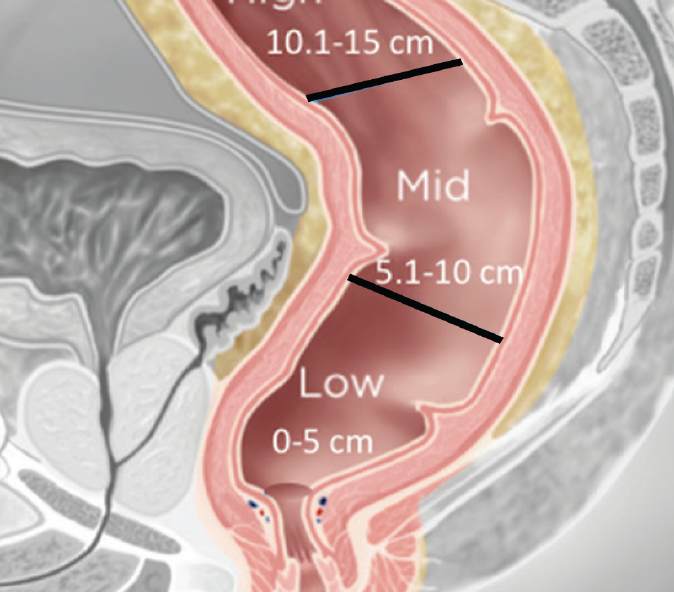

L’ECOGRAFIA-TRANSRETTALE E LA RISONANZA MAGNETICANELLA STADIAZIONE DEI TUMORI DEL RETTO BASSOsec. LA CLASSIFICAZIONE DI RULLIER E.

L’articolo presenterà lo studio prospettico condotto da Rullier E e coll, svolto su 404 pazienti con cancro del retto basso i quali saranno candidati per 4 diverse tipologie di intervento.